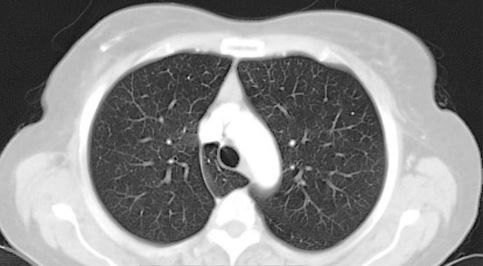

- DIAGNOSTICO PRECOZ DEL CANCER DE PULMON

- ECOGRAFIA PLEURAL Y PULMONAR